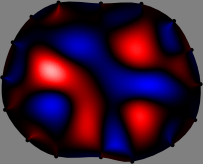

for [23]. This shows that the column vector is like an EEG (electroencephalography) data induced by dipole sources with directions at locations . Given that two dipole sources at distant locations produce mutually independent data, the correlation between and decreases with the distance between and . Fig. 2 shows a few images of the correlation as a function of for four different positions . The correlation decreases rapidly as the distance increases. In the green regions where the correlation is almost zero, is nearly orthogonal to .

Fig. 2 shows that if and are far from each other, the corresponding columns of the sensitivity matrix are nearly orthogonal. This somewhat orthogonal structure of the sensitivity matrix motivates an algebraic formula that directly computes the local ensemble average of conductivity changes at each point using the inner product between changes in the data and a scaled sensitivity vector at that point: